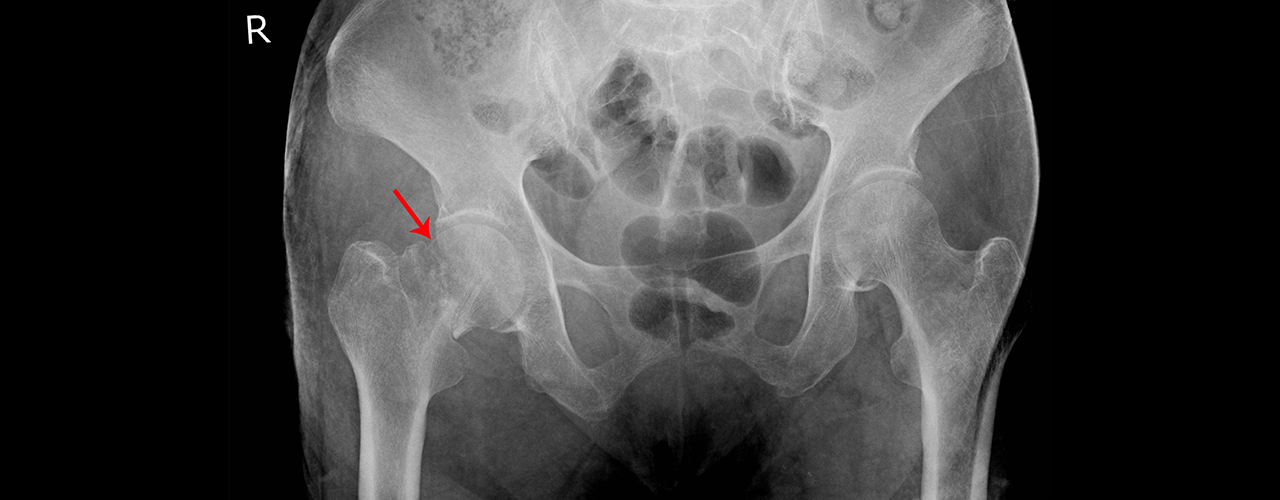

Pelvic Inflamatory Disease

Pelvic Inflammatory Disease (PID) is a condition, an infection of the female reproductive organs which if untreated can cause infertility.